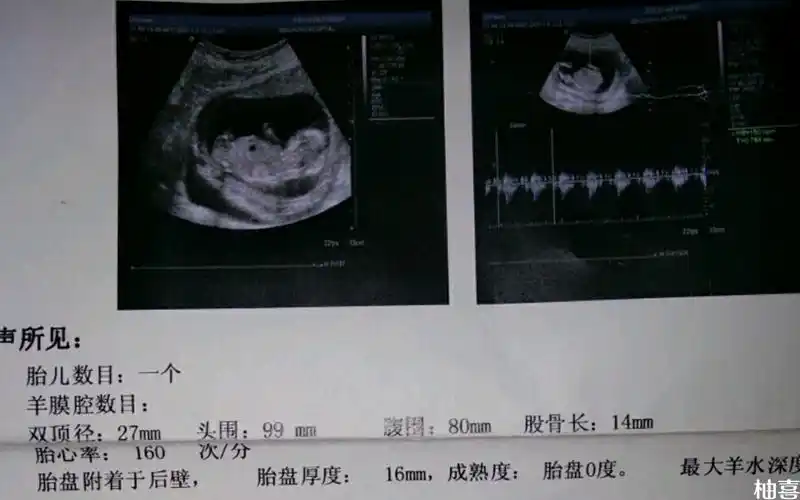

nt超声图像的单子上有圈圈是不是怀男孩的标志